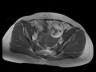

MR images demonstrate left ovarian mass containing fat and soft tissue. Left ovarian mass that contains: Fat (bright in T1 image and fat suppression in T1 fat sat and STIR images), soft tissue-dermoid plug (increased enhancement in T1+C fat sat images).

Conventional radiograph can show calcific and tooth components in the pelvis. An ovarian dermoid is seen as a unilocular cystic adnexal mass with some mural components on ultrasound. CT images demonstrate fat areas with very low Hounsfield values, fat-fluid level, calcification, Rokitansky protuberance. Pelvic MRI shows the presence of fat. Fat suppression technique is used to differentiate between ovarian dermoid cyst and hemorrhagic cyst. Dermoid cyst contains fat and its signal will be suppressed in T1 fat sat and STIR images (2, 3).